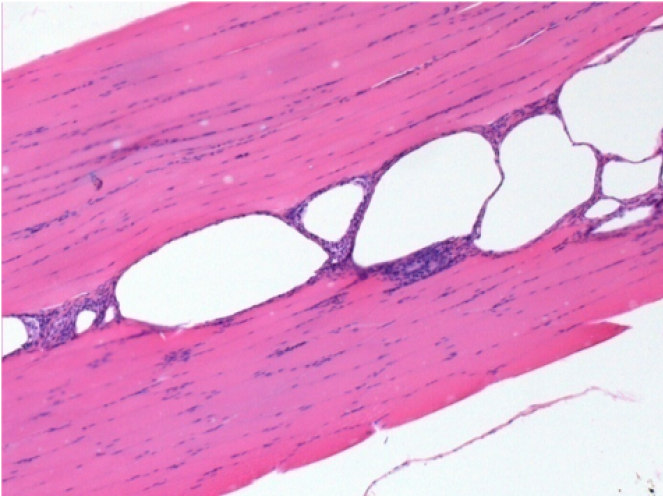

بعد 10 أيام من حقن إندوبيل

10 أيام بعد حقن إندوبيل 0.1 مل في العضلة أمام الظنبوب الأيمن.

هنا قد ترى تشكيل الفجوات التي تحيط بها الخلايا اللمفاوية. الفجوات تختلف عن نخر الأنسجة. يرتبط وجود الخلايا اللمفاوية بنفاذية أغشية الخلايا.

L : Control-100xD10

R:100xD10

R :200xD10

R :400xD10